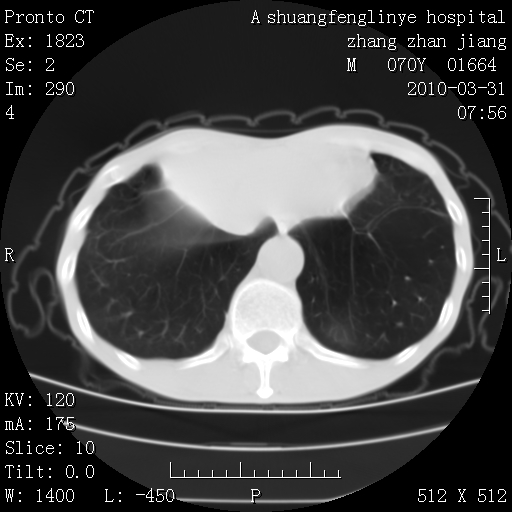

双上肺继发型tb并左上空洞形成,主动脉冠脉钙化。

支持:继发性肺结核伴空洞形成!建议纤支镜检查待出外周围型肺癌可能!

1)两肺上叶继发性肺结核并左肺上叶空洞形成。2)冠状动脉及主动脉钙化。